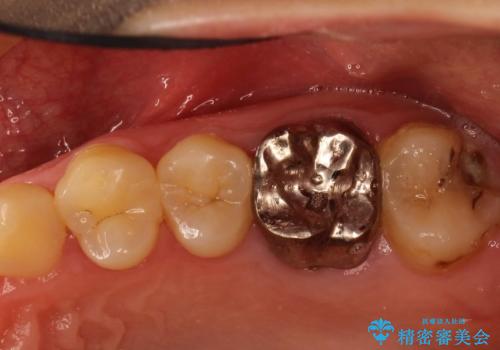

奥歯が割れてしまった! → インプラントによるかみ合わせの回復

歯がわれた 抜歯してインプラント 50代男性

左下奥歯 折れて抜歯 インプラントへ